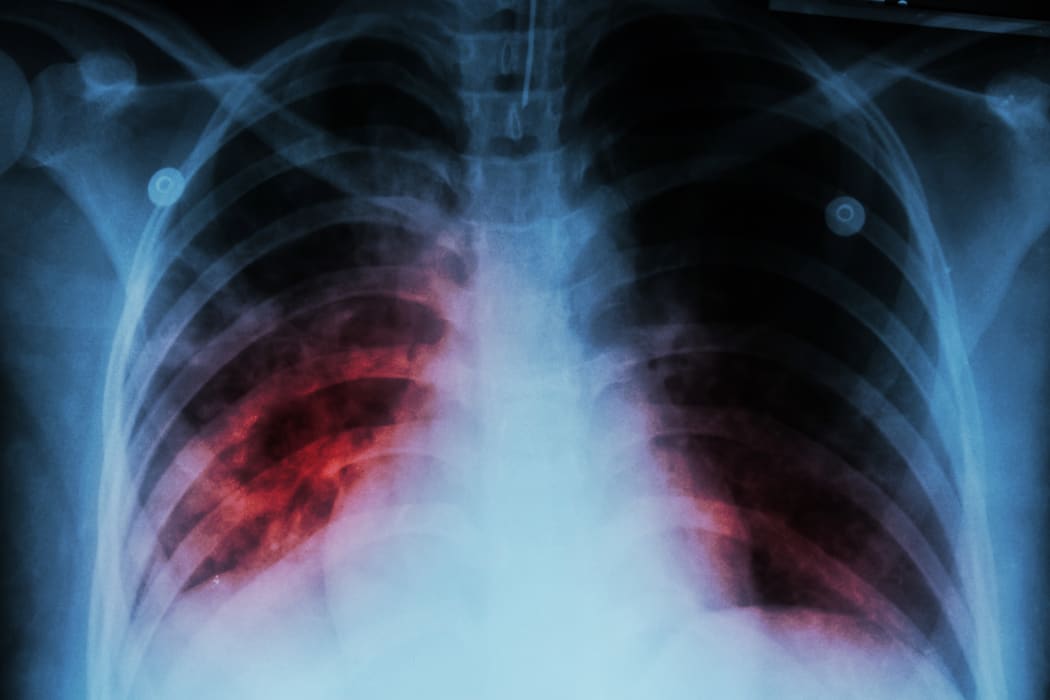

Pulmonary Tuberculosis ( TB )  :  Chest x-ray show alveolar infiltration at both lung due to mycobacterium tuberculosis infection

A chest x-ray showing alveolar infiltration at both lung due to mycobacterium tuberculosis infection. Photo: 123RF